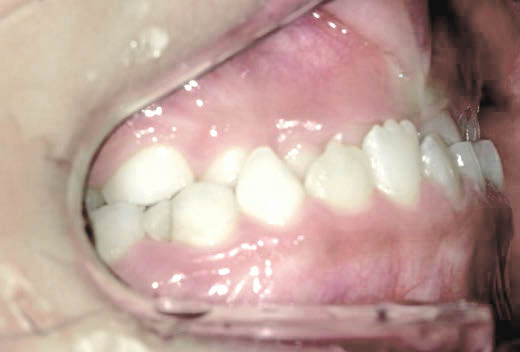

鼻がつまりやすく、口呼吸をしているために上あごが狭い状態でした。また上の前歯がかなり前へ傾いているため、お口をきちんと閉じていることができません。さらに、下の前歯もでこぼこしていました。

治療を終えて

装置によって上あごを拡大し、下あごを少し前へ成長させたことで、永久歯がきれいに並ぶスペースを確保しました。また、お口の機能が向上したことから鼻がよく通るようになり、口呼吸も改善され口も閉じやすくなったので顔の表情もよくなりました。

主訴・治療内容 下あごが後ろに下がり、出っ歯のようになっていることを心配して、無料相談に来院されました。